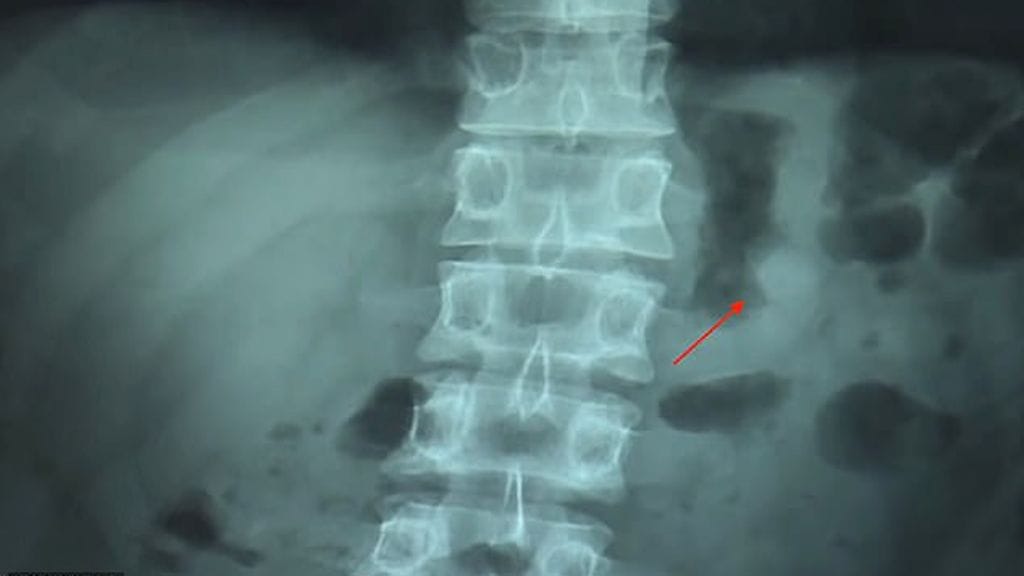

Taiwanilainen Ben Hsu oli torkahtanut kotisohvalleen AirPod-kuulokkeet yhä korvissaan. Herättyään mies ihmetteli, kun toista kuuloketta ei löytynyt, vaikka iPhonen paikannustoiminnon yhyttämän kuulokkeen heiveröinen piipitys kuuluikin. Lopulta Hsu ymmärsi äänen tulevan vatsastaan, johon kuuloke oli epähuomiossa päätynyt.